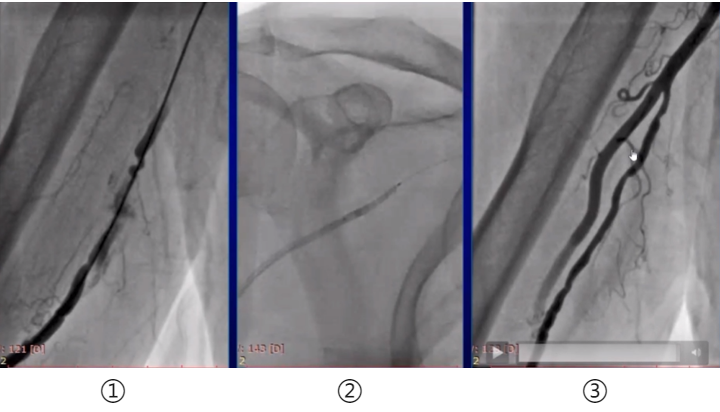

图①:痉挛,血管破裂,渗出相对较少,没痉挛的地方血管还是比较粗的,这个病人可以用BAT技术,导管是可以通过的。

图②:球囊放在导管里面,轻轻往上送

图③:做完PCI后回过来看,血管外渗已经完全消失

Case 3 高位桡动脉痉挛、破裂

高位桡动脉穿孔,痉挛,细小。使用BAT技术轻松上去,做好后,只剩下一点点痉挛,外渗消失。